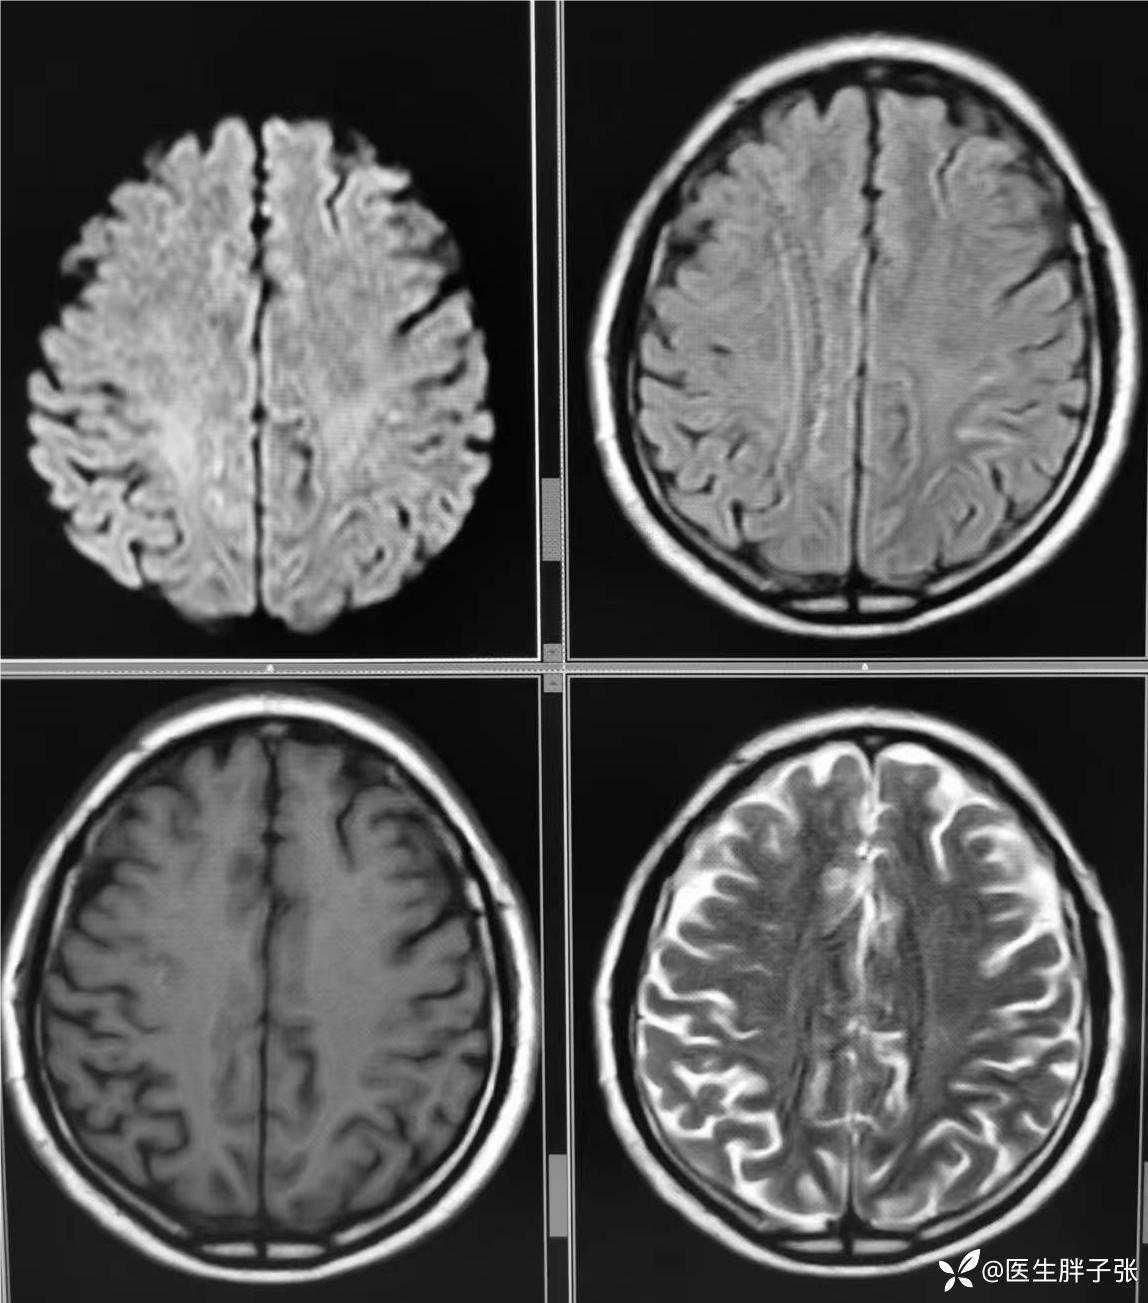

颅脑MR回报左侧顶叶新近梗死灶;多发腔隙性脑梗死及缺血灶;MRA未见异常。

再次查看核磁,考虑患者左侧顶枕叶及右侧枕叶脑组织存在混杂信号。